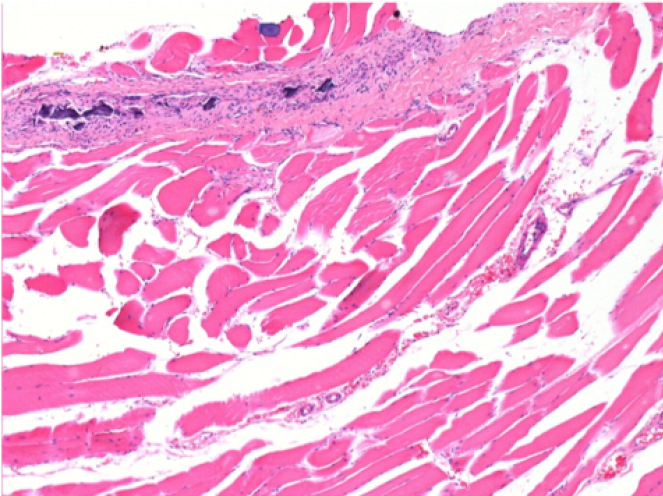

ol: Pretibial-Tedavi yok

Endopeel Enjeksiyonundan 10 gün sonra sağ pretibial kasta 0.1ml.

Burada lenfositlerle çevrili vakuollerin oluşumunu görebilirsiniz. Vakuoller doku nekrozundan farklıdır. Lenfositlerin varlığı, hücre zarlarının geçirgenliği ile ilgilidir.